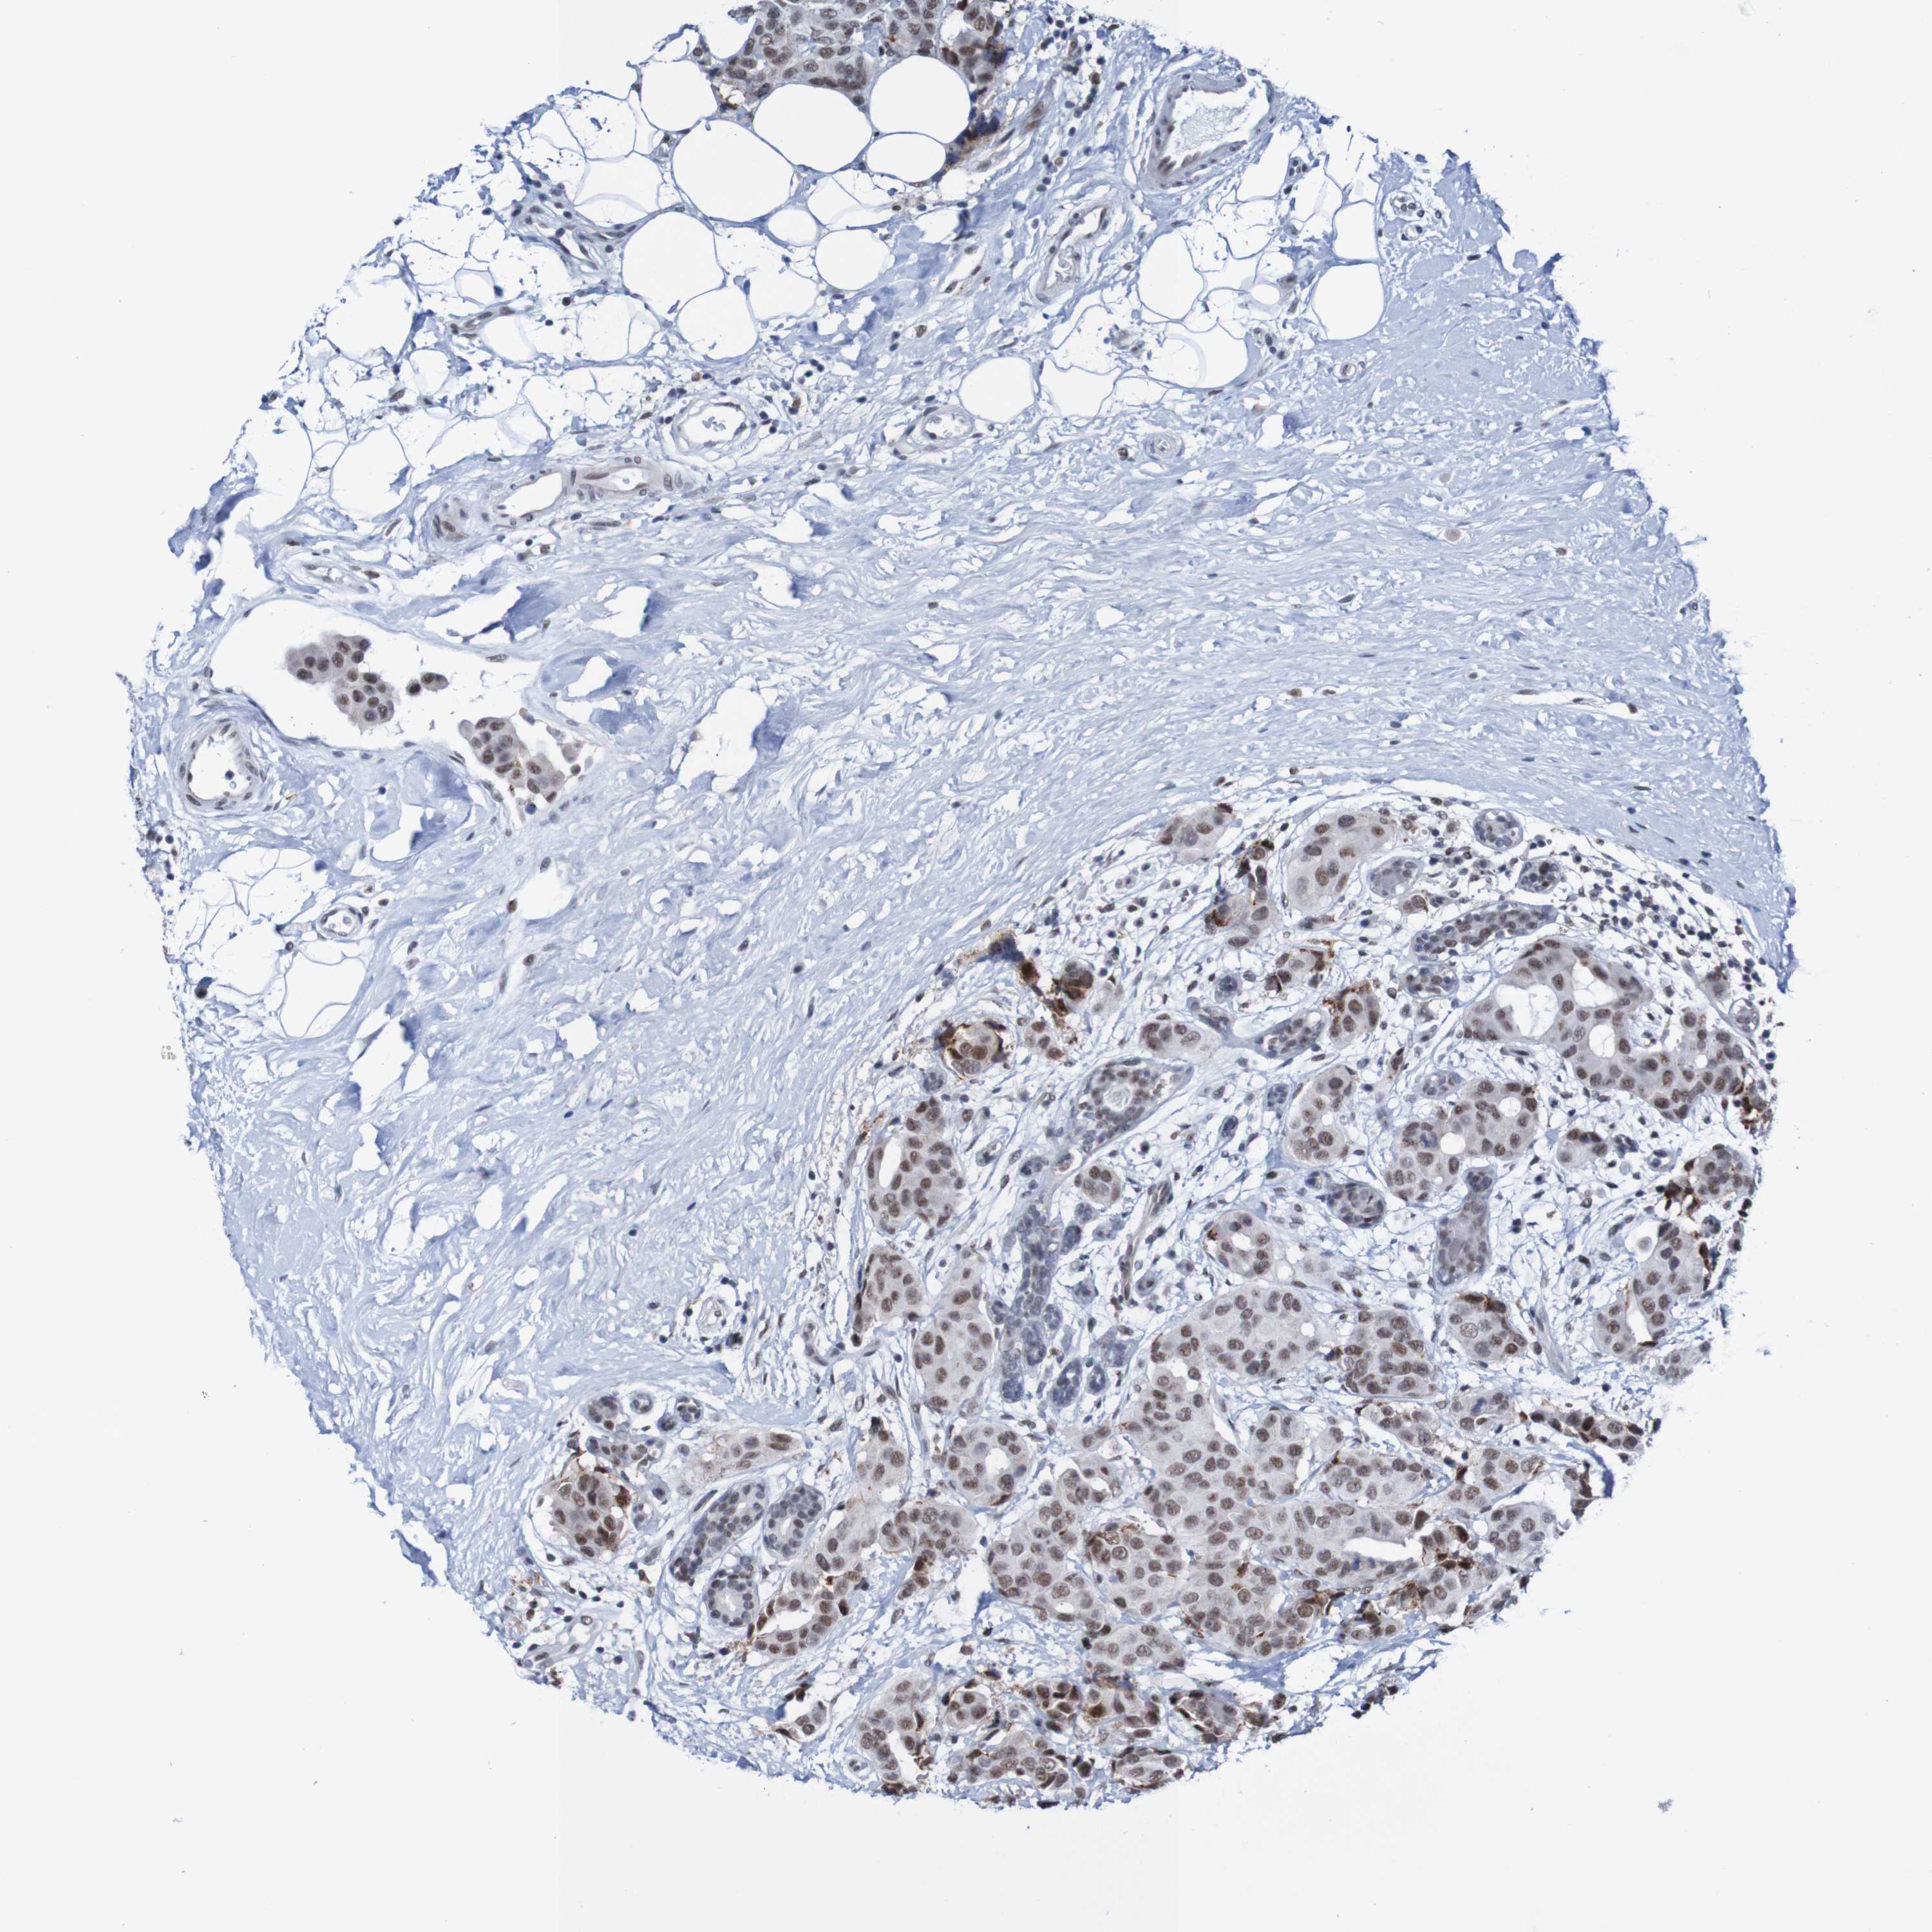

BRCA TCGA BRCA VALIDATION PROTEIN EXPRESSION